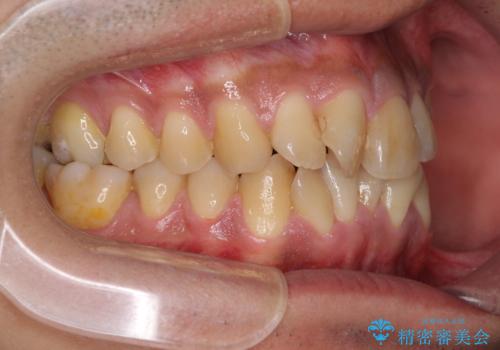

- 上下前歯の叢生を気にして来院された患者様です。

奥歯はクロスバイトとなっているので上顎は側方拡大を行いつつ、上下全体の叢生をインビザラインにより改善することとしました。